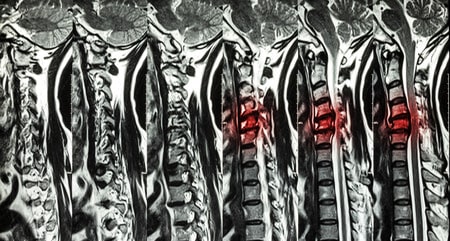

ESPONDILOLISTESIS CERVICAL

- Mielopatía cervical. Llamamos mielopatía cervical a la afectación de la médula por una compresión. La mielopatía produce alteraciones en brazos y piernas, alteraciones de la marcha, pérdida de control de esfínteres e hiperreflexia.

Como ocurre con la espondilolistesis a nivel lumbar basta una simple radiografía para llegar al diagnóstico. Con las radiografías en flexión y extensión determinaremos el grado de inestabilidad, si el movimiento de la vértebra es menor de 2,, estaremos ante una inestabilidad leve y si es mayor de 4 mm será una inestabilidad severa.